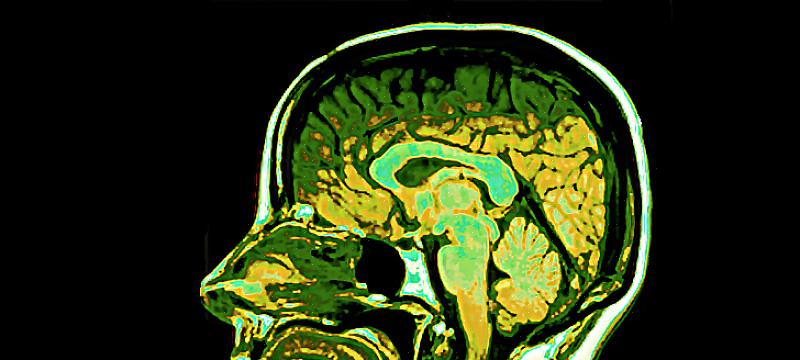

פסיכוביולוגיה: חקר המוח וההתנהגות

פסיכוביולוגיה היא ענף בפסיכולוגיה. לכן, מטרתו העיקרית היא חקר ההתנהגות. עם זאת, לגישתו יש מאפיין מיוחד המקנה לו את שמו – ביולוגיה. מסיבה זו, מאז הקמתו במאה ה-19, הוא בולט במחקר של תהליכים נפשיים דרך אלמנטים ורמות אורגניות שונות.